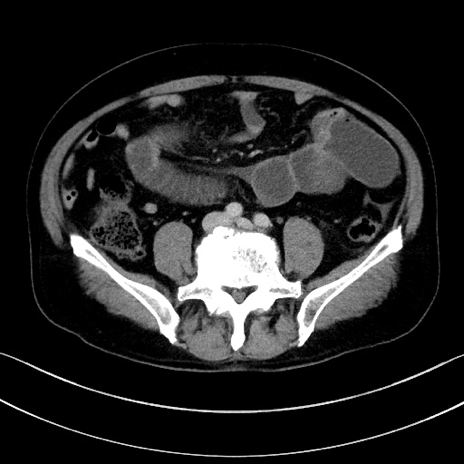

冠状断像

【症例】70歳代男性

【主訴】腹痛

【現病歴】今朝から腹痛あり。全体的に痛い。特に左上の方。排ガスが今日はない。冷や汗が出る。

【既往歴】直腸癌術後

【身体所見】左側腹部〜上腹部に圧痛あり。腹膜刺激症状明らかなではない。軽度反跳痛。左下腹部に術後瘢痕あり。

【データ】WBC 7700、CRP 0.02